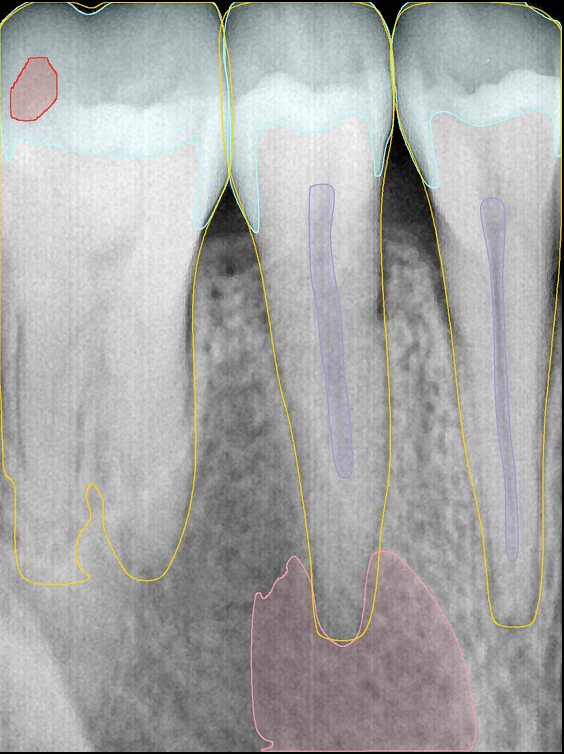

第二版算法问题测试

| 第一版 | 第二版 | 是否解决 | |

|---|---|---|---|

![]() | ![]() ![]() 边角识别有问题 龋齿识别不全 牙髓识别不全 | ![]() | 解决 |

![]() | ![]() 边角识别有问题 识别信息有误 自查(牙冠识别不全) | ![]() | 解决 |

![]() | ![]() ![]() 边角识别有误 大范围填充识别遗漏 | ![]() | 解决 |

![]() | ![]() 识别信息不全 | ![]() | 解决 |

![]() | ![]() ![]() 边角问题 牙胶识别不全 牙冠识别不全 | ![]() | 解决 |

![]() 换图片 | ![]() | ![]() 牙冠部分稍微白了一些就识别成小范围修补,部分判断异常 | 部分解决,修复类略敏感,牙冠部分稍微白了一些就识别成小范围修补,部分判断异常。 |

![]() | ![]() ![]() 牙冠识别不全 牙髓不全 根尖炎龋齿识别有误 | ![]() | 解决 |

![]() | ![]() | ![]() | 解决 |

![]() 换图片 | ![]() | ![]() | 解决 |

![]() | ![]() 牙冠识别有误 | ![]() | 解决 |

![]() 换图片 | ![]() ![]() 边角识别有误 | ![]() 修复类敏感 | 部分解决,图像过白,导致修复类判断异常。 |

![]() 换图片 | ![]() 牙冠识别不全 | ![]() 修复类敏感 | 部分解决,图像过白,导致修复类判断异常 |

结论:修复类出现了不鲁棒的情况,后续需要加入轮廓的扩充数据进行增强。